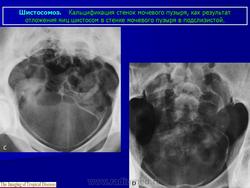

Бильгарциоз (Schistosomiasis) мочевого пузыря